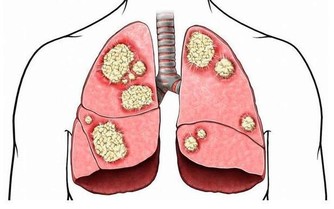

我問何故?他說,蘑菇雖好,但有個很重要的特點,就是對重金屬的富集能力特強,最多可以達到100多倍。

幾乎所有重金屬,如鉛、汞、鎳等等等等所有的重金屬,蘑菇都會富集。

但是,我們人體卻沒有排出重金屬的機制。

久之這些重金屬就會在腎小管內聚集,嚴重時甚至會引起腎小管的壞死。

對於在這些受到污染的水土上生長起來的蘑菇來說,可以肯定地是,它們會對土壤、水和空氣中的重金屬有富集作用。

我們吃下去之後,這些重金屬就會沉積在我們的腎小管內,久而久之,就會傷及我們的腎臟。

一旦我們再有個高血壓、糖尿病什麼的毛病,腎臟的代償能力會進一步下降。